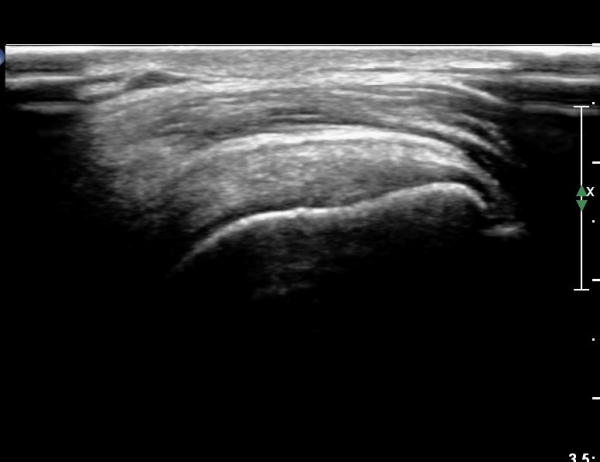

ÃÊÀ½ÆÄ ¼Ò°ß :  ÀÌµÎ¹Ú±Ù°Ç È¾´Ü¸é°Ë»ç¿Í ±Ø»ê°Ç Á¾´Ü¸é°Ë»ç¿¡¼­  ƯÀÌ ¼Ò°ß ¾øÀ½(»çÁø 1, 2).